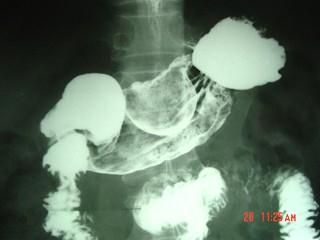

男,52岁,中上腹痛,影像检查如图,最可能的诊断是()A.慢肥厚性胃炎B.胃癌C.胃溃疡D.胃平滑肌瘤E.胃平滑肌肉瘤

问题 男,52岁,中上腹痛,影像检查如图,最可能的诊断是()

选项 A.慢肥厚性胃炎 B.胃癌 C.胃溃疡 D.胃平滑肌瘤 E.胃平滑肌肉瘤

答案 D